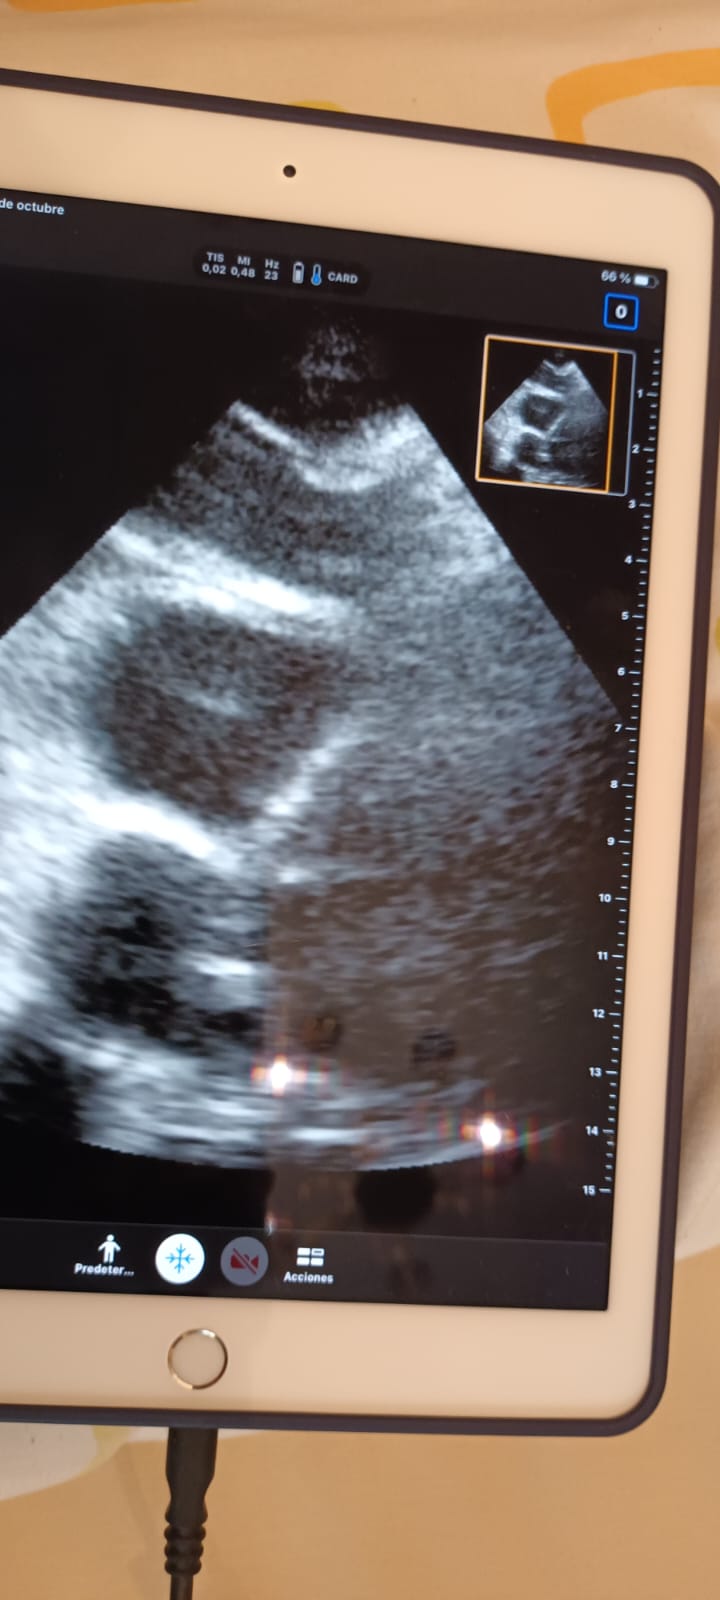

Realizamos también ecocardioscopia, encontrando un trombo en transición en ventrículo derecho.

Trombosis venosa profunda en miembro inferior derecho y posible trombo en transición en ventrículo derecho.